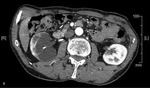

Proces zapalny obejmujący torbiel nerki może dać bardzo różnorodny obraz (zmiana charakteru płynu w obrębie torbieli znajduje odbicie w badaniach obrazowych). Obwodowe wzmocnienie pokontrastowe może wręcz potwierdzać występowanie ropnia.1 Tej koncepcji przeczy jednak stan kliniczny pacjenta i brak odchyleń od normy w badaniach laboratoryjnych. Rak nerkowokomórkowy przeważnie jest guzem o charakterze litym, jednak w ok. 20% przypadków może zawierać także elementy torbielowate.1 Obecność wzmocnienia obwodowego w fazie pokontrastowej badania TK, zwłaszcza rozmieszczonego nieregularnie, zawsze musi budzić podejrzenie rozrostu nowotworowego. U pacjenta, którego przypadek jest opisywany, na podstawie wyników badania histopatologicznego rozpoznano raka nerkowokomórkowego. Innym przykładem guza nowotworowego o charakterze torbielowatym, który może występować w obrębie nerki, jest torbielakogruczolak, znany także jako nerczak torbielowaty wielokomorowy. Guz najczęściej stwierdza się u małych chłopców i kobiet w wieku 40-70 lat (inaczej niż w prezentowanym przypadku). Składa się on z licznych torbieli wypełnionych śluzowatą treścią. W obrębie guza często występują zwapnienia (szacuje się, że w 10-50% przypadków), natomiast obszary krwotoczne lub martwicy, zazwyczaj obserwowane w rakach nerkowokomórkowych, w nerczakach torbielowatych są rzadkie. Kielichy i miedniczka nerki bywają modelowane przez torbiele, które nie komunikują się z układem wydalniczym. Po podaniu środka kontrastowego wzmocnieniu ulega lita część guza.1 Typowy obraz TK torbielakogruczolaka nerki zaprezentowano na rycinie 3A-C.